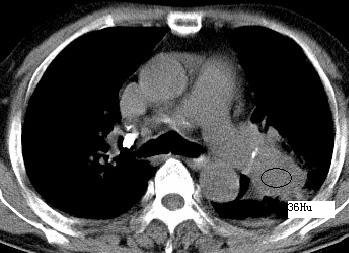

以下是引用xianxianzhongyi在2008-4-20 14:44:00的发言:[br]本人愚见:次病例短短两月的时间,呈现如此大面积实变,病变增长过于迅速,此其一。其二,病变在动脉早期既有明显强化。其三,左上叶后段及下叶背段多叶受累。其四,肺门及纵隔内未见明显肿大的淋巴结。估计层面较厚段支气管显示不清。 诊断:炎性实变可能性大。

以下是引用光影相伴在2008-4-20 14:39:00的发言:[br]支持:1)左侧中央型肺癌伴左肺上叶阻塞性肺炎。、[br] 2)双侧少量胸腔积液。